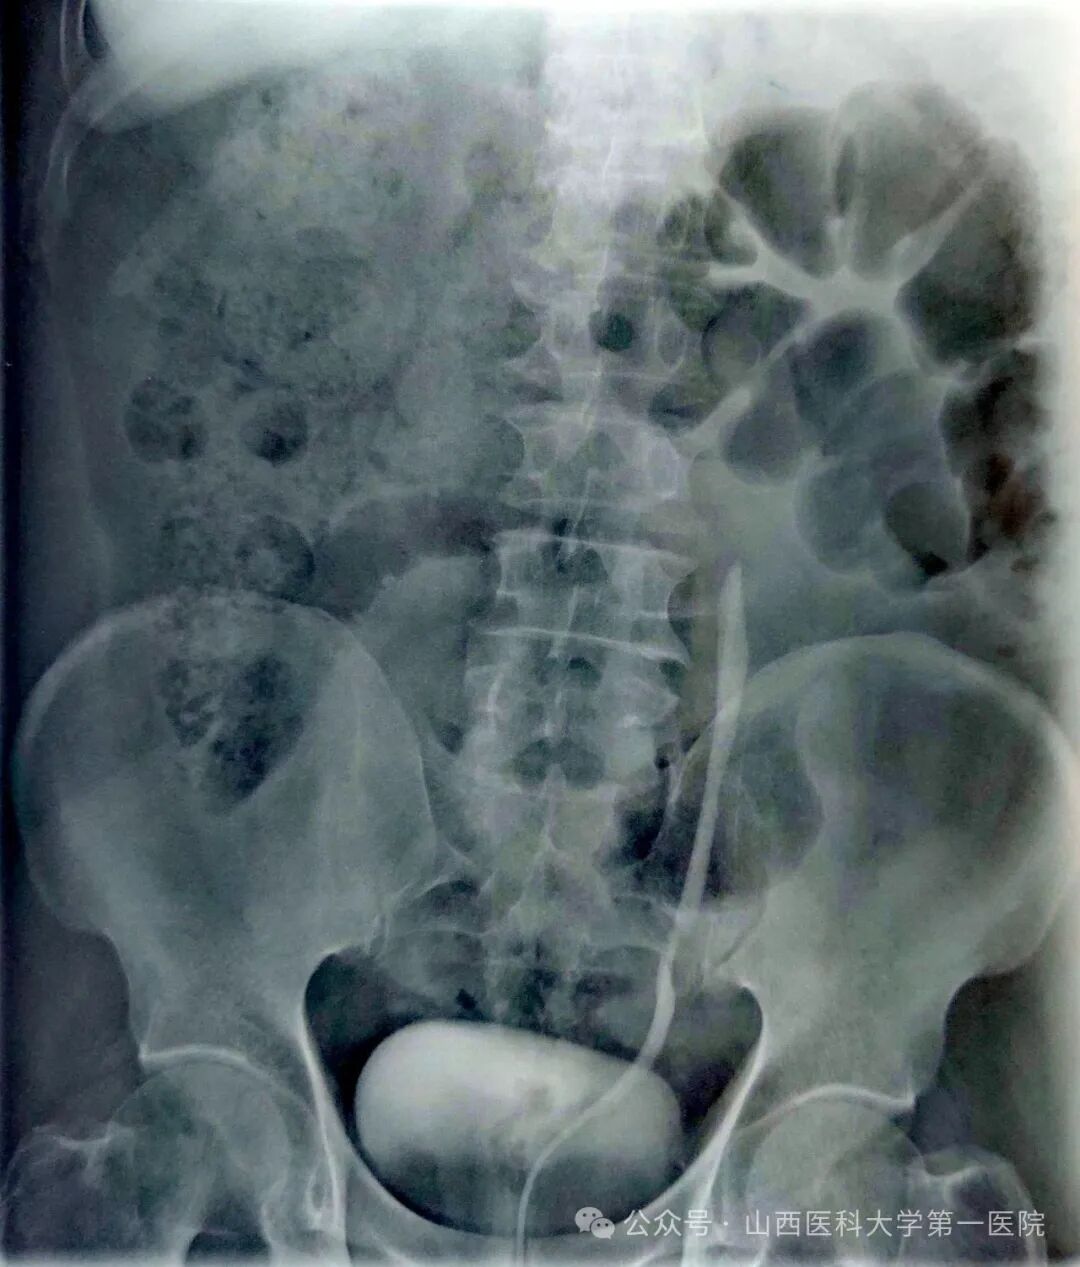

55岁男性患者,2024年3月因“左侧输尿管结石”在外院行输尿管镜碎石术;2024年9月在外院诊断为“左侧输尿管上段狭窄”,狭窄段长约3cm,行“开放左侧输尿管成形术”,术后半年拔除输尿管支架管,复查显示肾积水无改善;2025年4月,为求进一步诊治就诊于山医大一院,经影像学检查明确诊断为“左侧输尿管上段狭窄”,此次狭窄段长约1cm,位于既往手术区域。

术前逆行造影